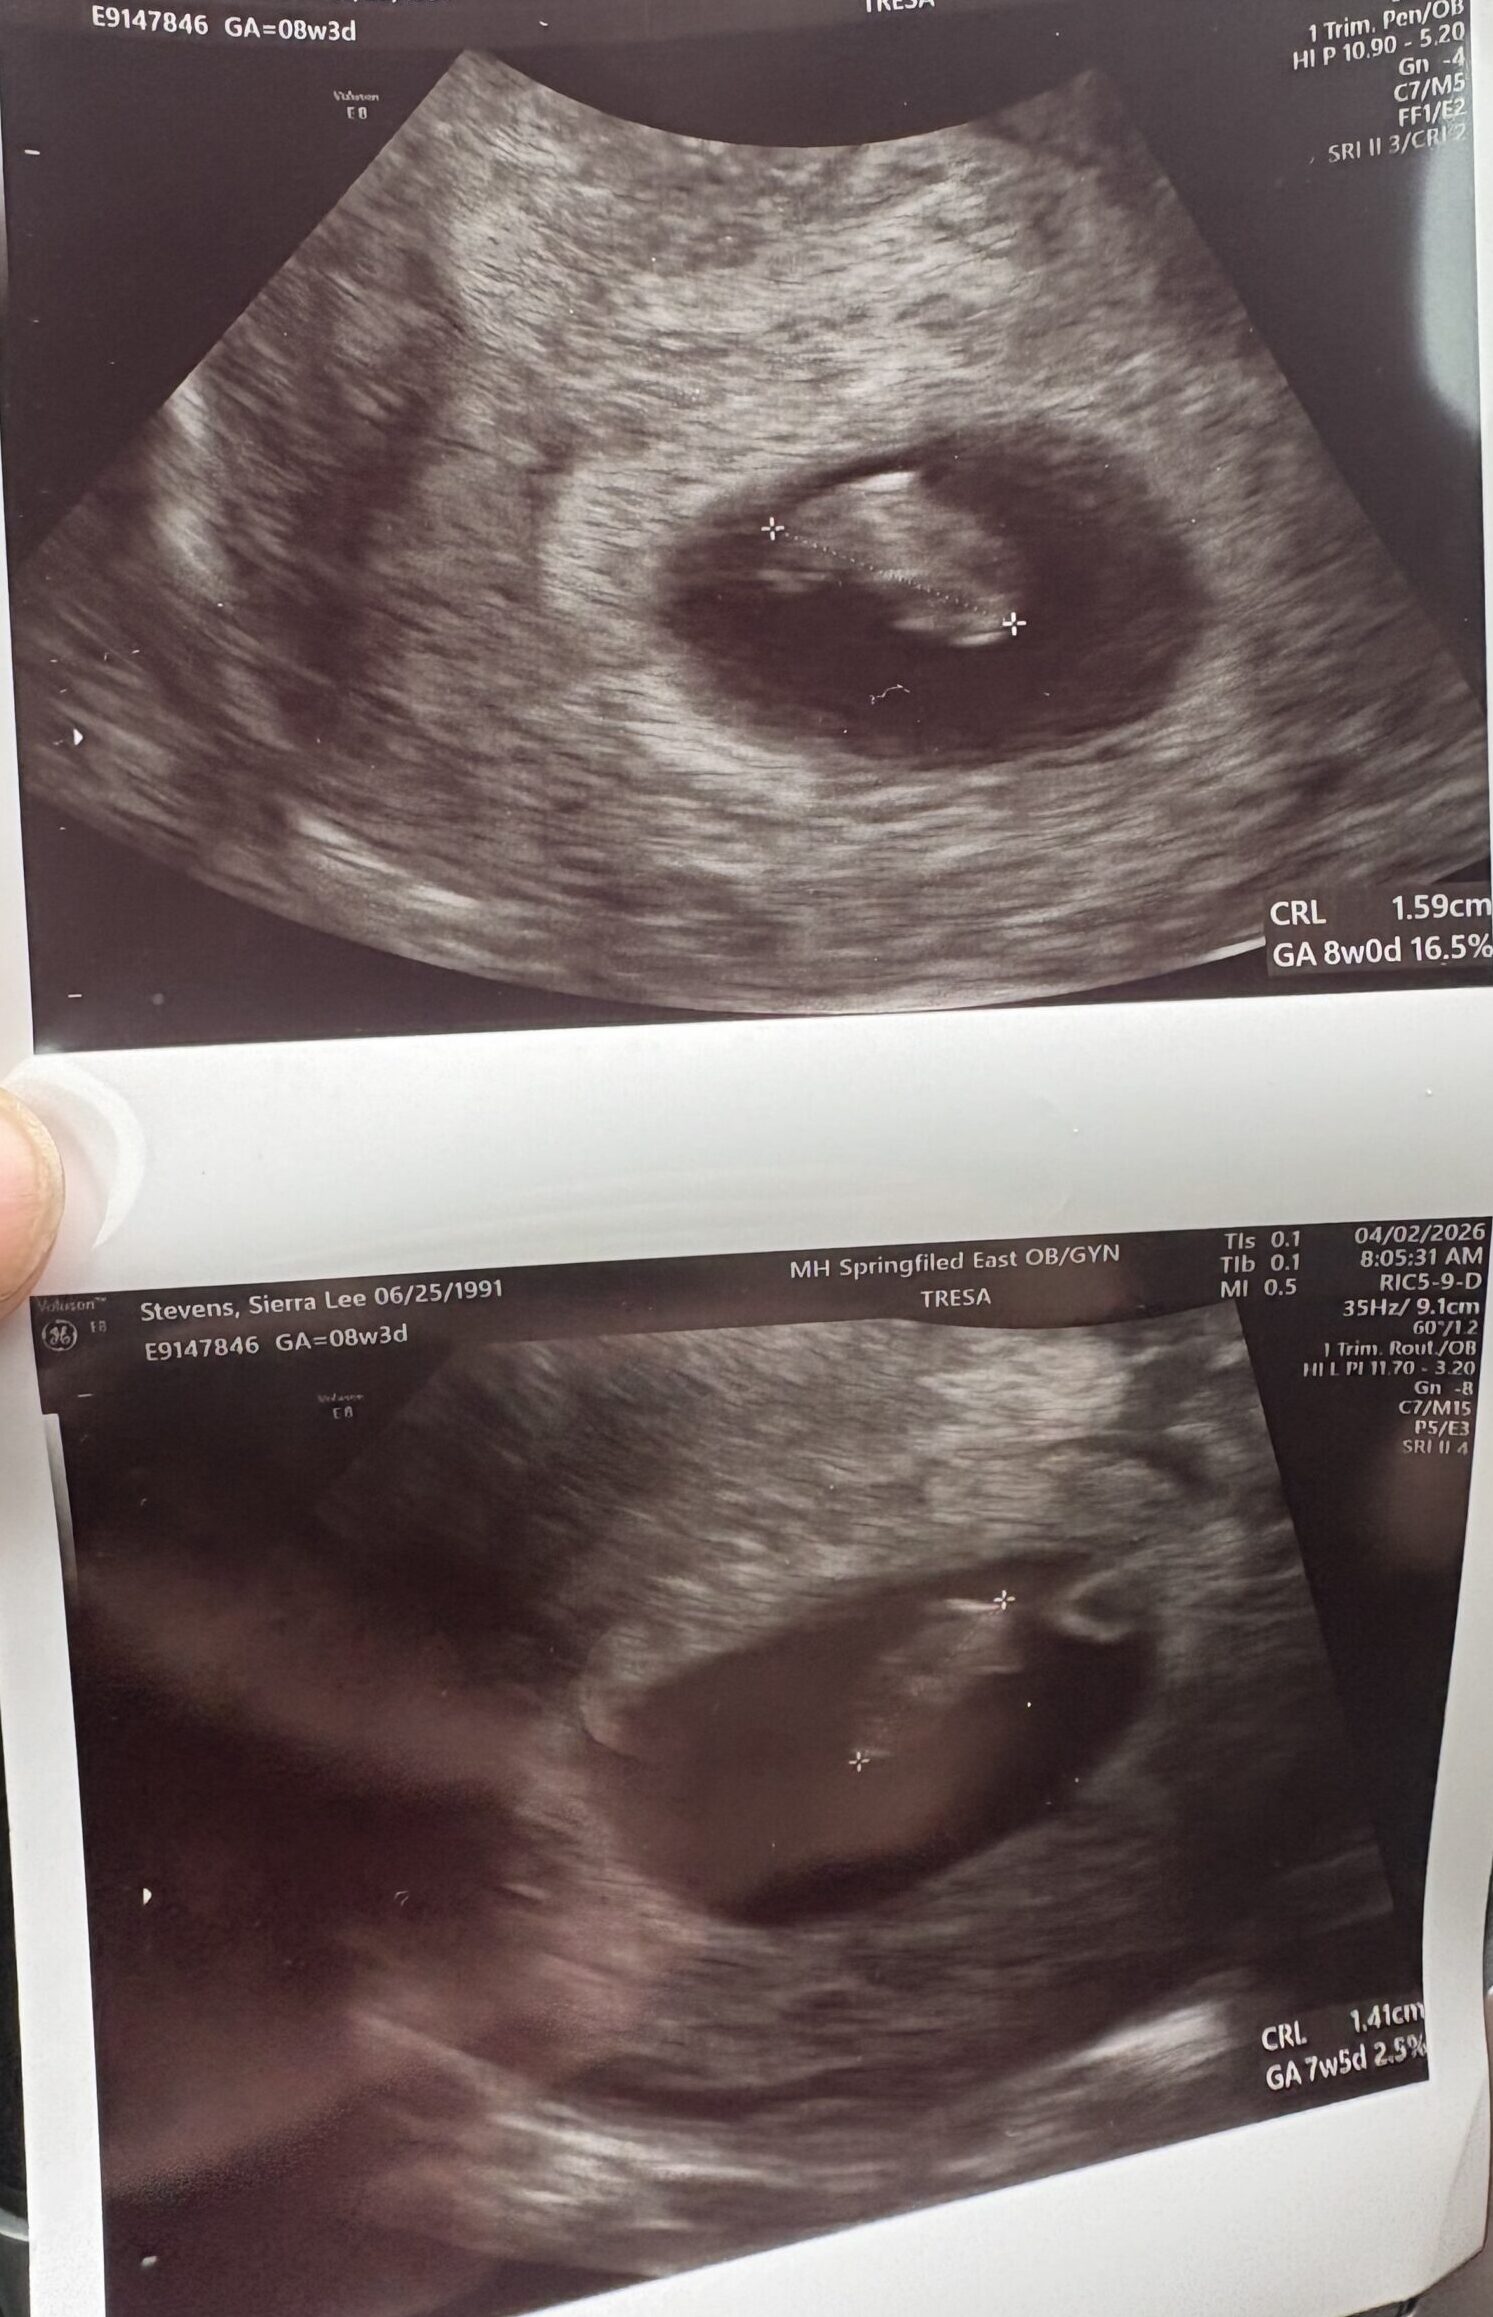

Springfield, OhioThis is are first after surgery

– Tubal Reversal Surgery 9/2025

– Due Date 11/2026

Patient age: 34

Tubal ligation type: Resection (tied or cut)

Patient hometown: Springfield, Ohio